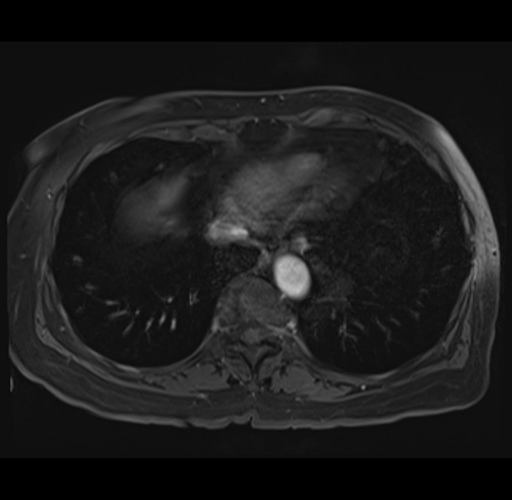

MRI T1

Imaging analysis

Based on your CT findings, which issue(s) would give reason for "planned slowing down moment(s)" in this case?

Considering a standard right hepatectomy procedure, what step(s) of the operation would you do differently in this case?